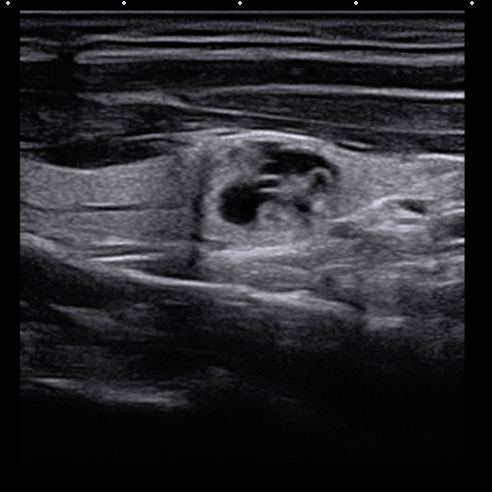

02、看边界

1. 清晰:结节与周围甲状腺组织界限清楚,提示趋向于良性结节可能性大。

2. 不清晰:结节与周围甲状腺组织界限不清,提示趋向于恶性肿瘤可能性大。

甲状腺结节超声图像

03、看形态

1. 形态规则:提示趋向于良性结节可能。

2. 形态不规则:提示趋向于恶性结节可能。甲状腺癌结节多具有“侵略性”的扩张性或侵润性生长,呈现为“张牙舞爪”的分叶状或成角畸形。

甲状腺结节测量